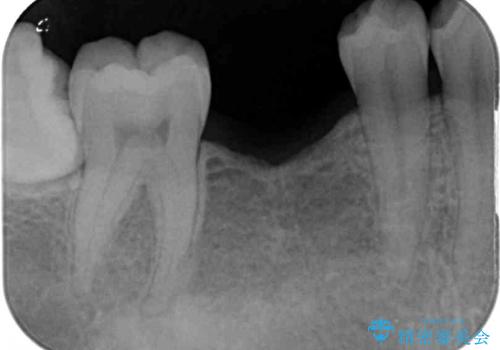

欠損部位の骨や歯肉の状態は非常に良く、速やかにインプラント埋入を行い、補綴治療を進めて行くことのできる状態でした。